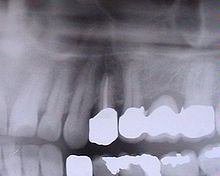

Bridge 3 éléments (dents nos 25, 26, 27)

Bridges

Un bridge (pont au Québec[3]) ou prothèse partielle fixe[1] permet de remplacer une dent absente, voire deux, en s'appuyant sur les dents adjacentes (une de chaque côté) ; au-delà le risque de fracture est trop élevé. Mais on peut également réaliser un bridge de plus grande portée, en prenant appui sur plusieurs dents piliers. Le principe est le même que pour la couronne.